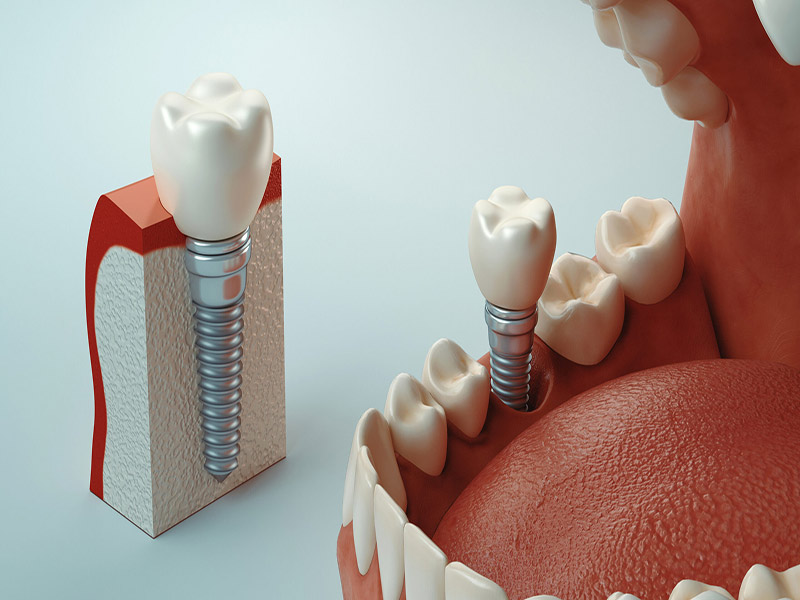

ایمپلنت دندان بهعنوان یکی از پیشرفتهترین روشهای جایگزینی دندانهای از دست رفته، مزایای بسیاری از جمله دوام بالا و ظاهر طبیعی دارد. با این حال، برخی بیماران پس از کاشت ایمپلنت با حساسیتهایی مانند درد خفیف، احساس ناراحتی یا واکنش به دمای سرد و گرم مواجه میشوند. این حساسیتها اگرچه معمولاً موقتی هستند، اما در صورت عدم مدیریت صحیح میتوانند تجربه ناخوشایندی ایجاد کنند. در این مقاله از وب سایت دکتر رضا شهریاری، به عنوان بهترین دندانپزشک در مشهد به بررسی روشهای مؤثر و علمی برای جلوگیری از حساسیت بعد از ایمپلنت دندان میپردازیم. پس تا پایان مقاله با ما همراه باشید.

حساسیت پس از کاشت ایمپلنت معمولاً به دلیل التهاب لثه، فشار بر اعصاب اطراف، یا واکنش طبیعی بدن به جراحی ایجاد میشود. این علائم ممکن است شامل درد ضرباندار، سوزش لثه، یا حساسیت به غذاهای سرد و گرم باشد. اگرچه این موارد اغلب در روزهای اول پس از جراحی رخ میدهند و بهتدریج کاهش مییابند، اما رعایت نکات پیشگیرانه میتواند شدت و مدت آنها را به حداقل برساند. در ادامه، راهکارهای عملی برای جلوگیری از این مشکل را مرور خواهیم کرد.